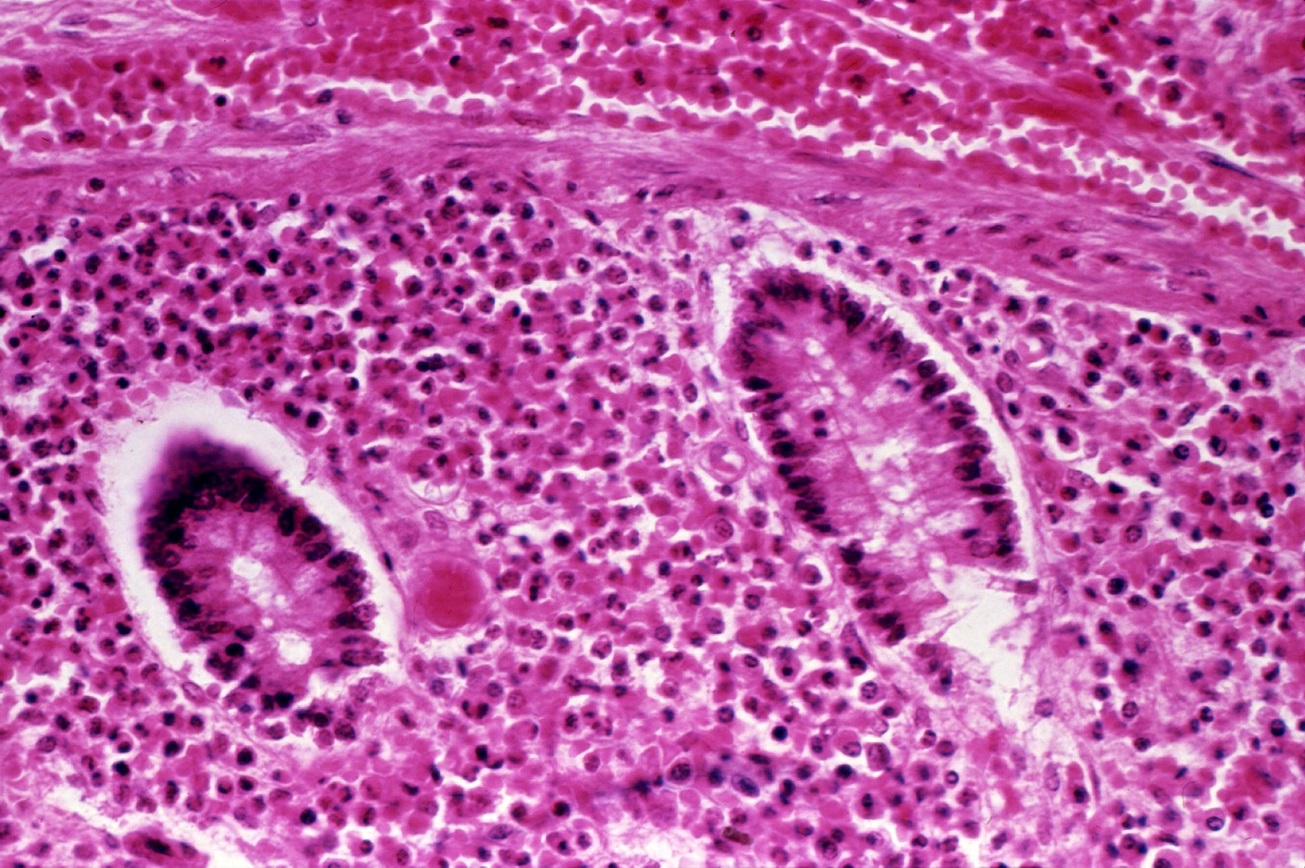

Introduction anthrax is an ancient zoonotic disease which primarily infects herbivores with humans occasionally being infected. Cutaneous anthrax is easy to cure if it is treated early with appropriate antibiotics. It is excellent for use in case.

How is anthrax in humans treated? If a domestic animal is sick or has just died, can its meat and. Patients with serious cases of anthrax need to be hospitalized.